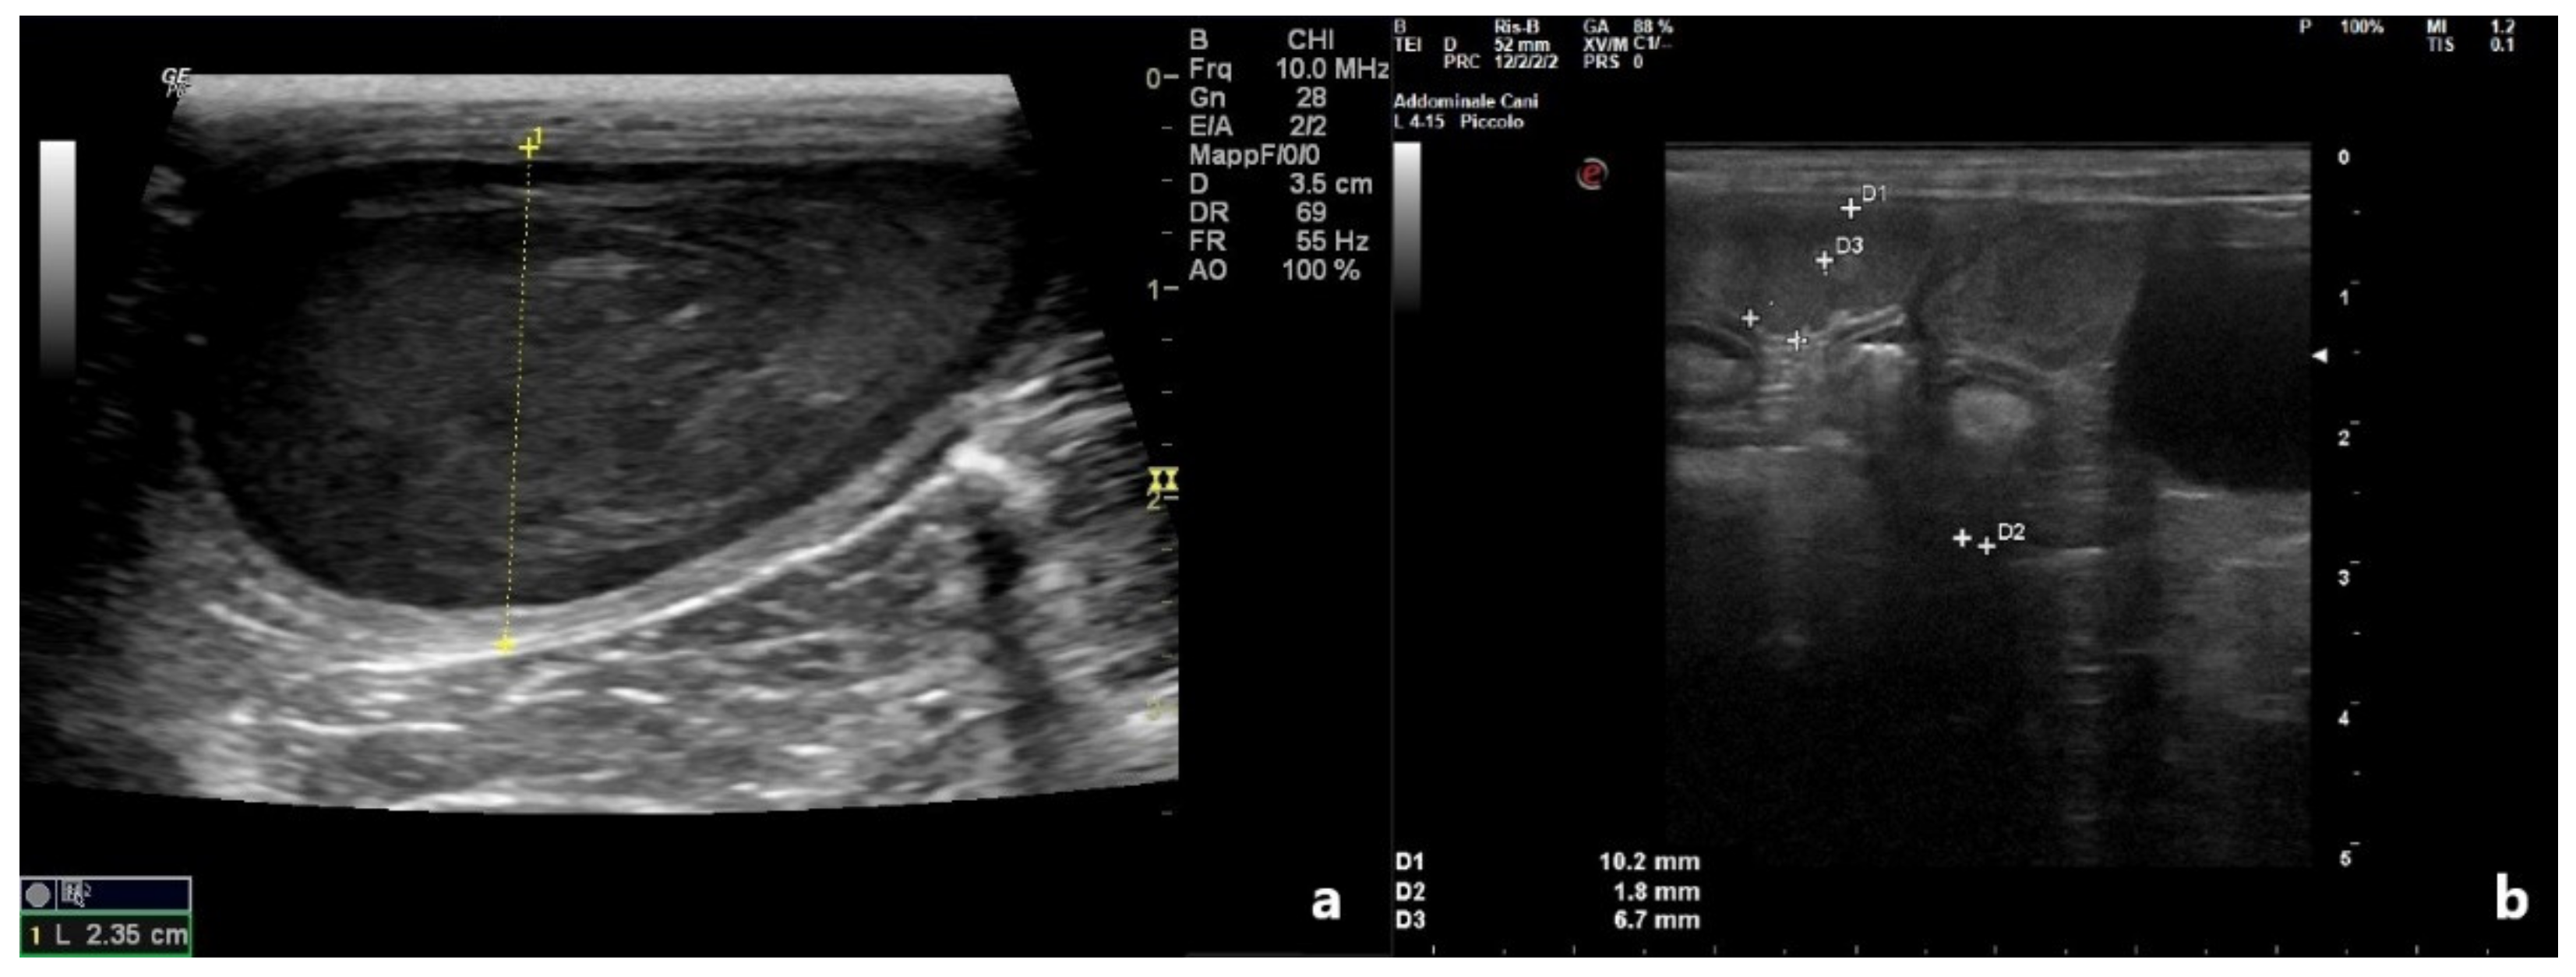

| Uterine Diameter (cm) | Uterine Wall (cm) | Luminal Collection | ||||

|---|---|---|---|---|---|---|

| D0 | D10 | D0 | D10 | D0 | D10 | |

| Patient 1 | 0.75 | 0.49 | 0.2 | 0.05 | Hypoecoic | No |

| Patient 2 | 2.35 | 0.57 | 0.3 | 0.10 | Heterogeneous | No |

| Patient 3 | 0.41 | 0.23 | 0.1 | 0.1 | Anechoic | No |

| Patient 4 | 1.02 | 0.56 | 0.18 | 0.10 | Anechoic | No |

| Patient 5 | 0.80 | 0.37 | 0.15 | 0.10 | Hypoecoic | No |